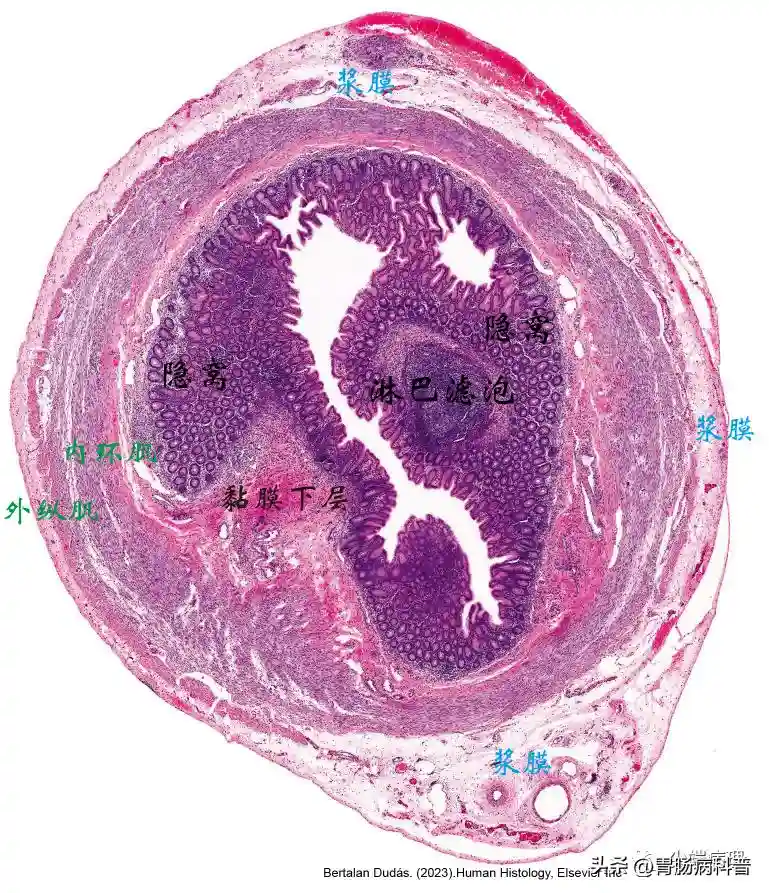

阑尾组织结构图

阑尾被覆有大肠黏膜,黏膜上皮由柱状细胞及杯状细胞组成,它们延伸入Lieberkühn隐窝,黏膜下层含有淋巴滤泡。肌层由内环形平滑肌层以及外纵行平滑肌层组成,最外层为浆膜。